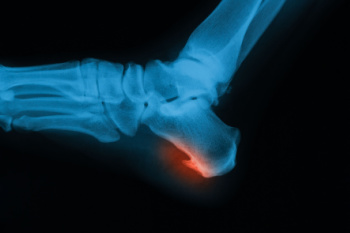

Symptoms

- Warped or oddly shaped nails

- Yellowish nails

- Loose/separated nail

- Buildup of bits and pieces of nail fragments under the nail

- Brittle, broken, thickened nail

Treatment

If self-care strategies and over-the-counter medications does not help your fungus, your podiatrist may give you a prescription drug instead. Even if you find relief from your toenail fungus symptoms, you may experience a repeat infection in the future.

In some cases, surgical procedure may be needed to remove the toenail fungus. Consult with your podiatrist about the best treatment options for your case of toenail fungus.